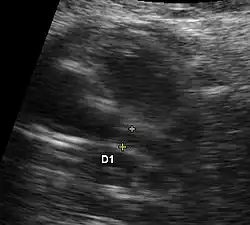

Aspects échographiques avant la naissance

Plusieurs aspects peuvent se rencontrer: une hypertrophie ou une hypoplasie du ventricule gauche ou un ventricule gauche quasiment sans aucune contraction sans aucun flux sanguin au doppler. La circulation du sang étant alors uniquement assuré par le ventricule droit. Le pronostic de cette maladie dépendra du ventricule droit. La visualisation directe d'une ouverture incomplète de la valve aortique et la présence de turbulence au niveau aortique par doppler couleur sont les deux signes directes de cette pathologie mais difficiles à visualiser lors de l'échographie obstétricale. Une brillance anormale du ventricule gauche est un signe de souffrance myocardique par diminution du flux sanguin des coronaires.